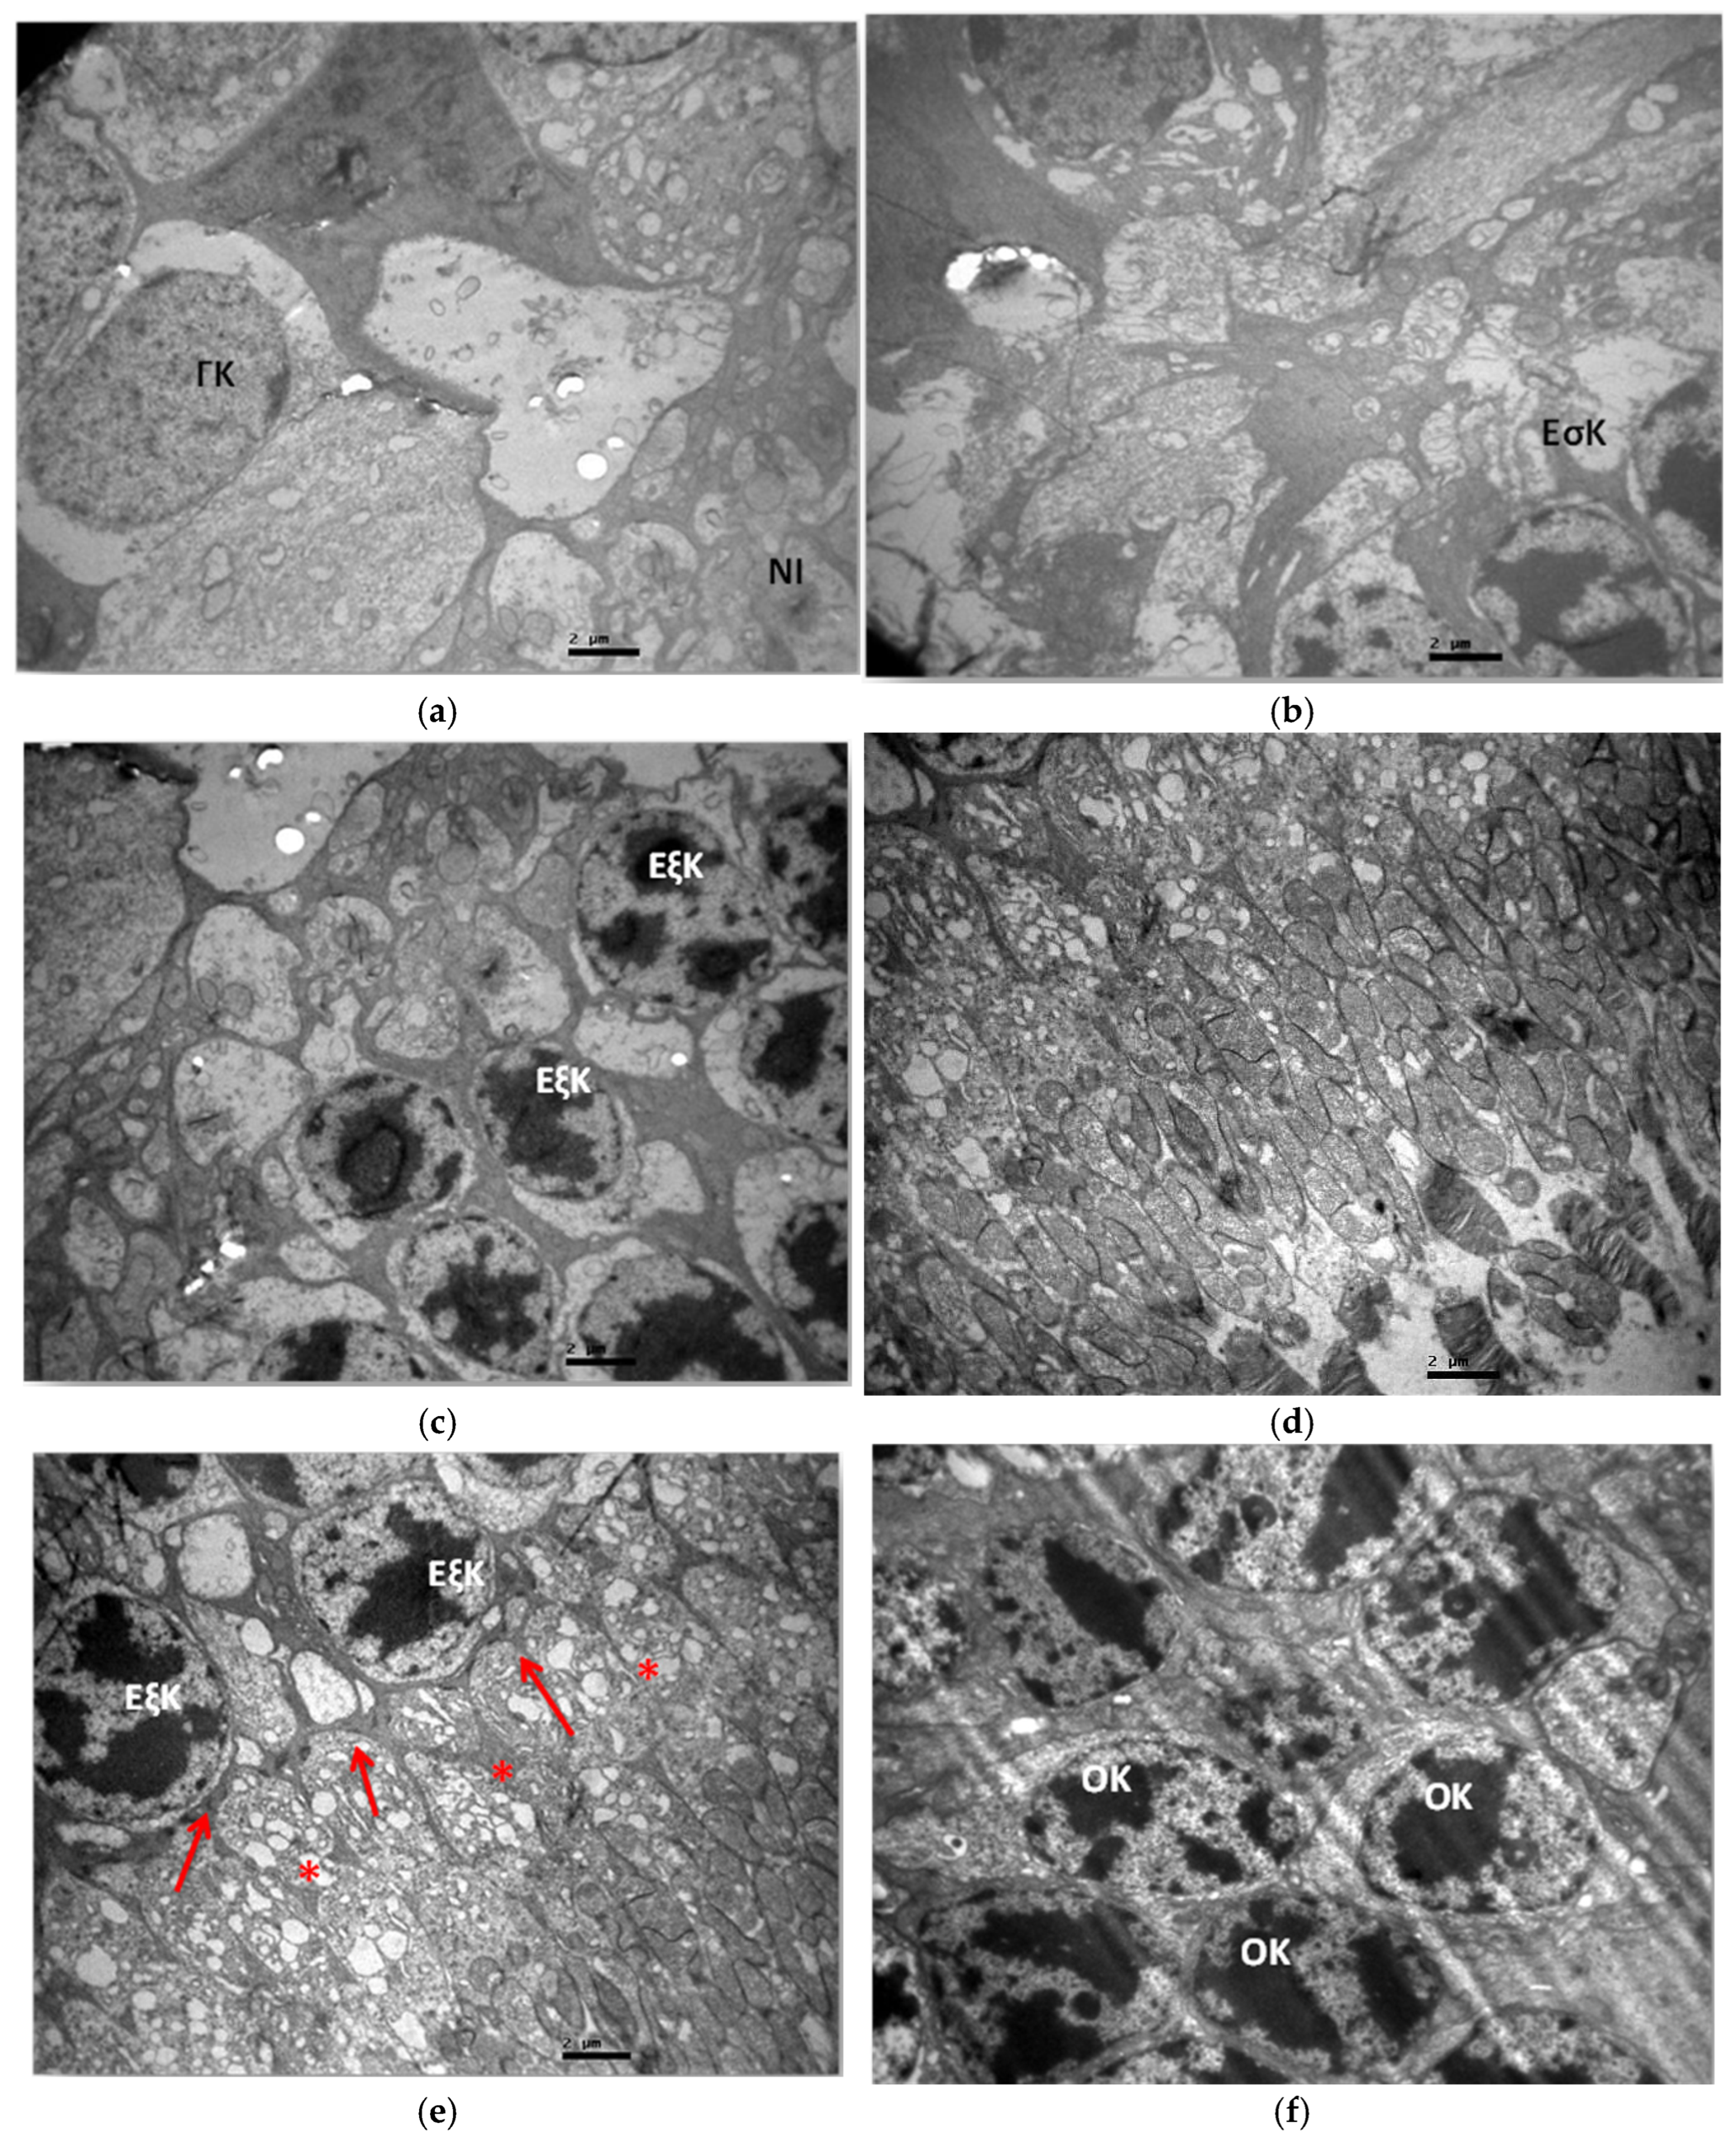

3.2.1. Group C2

3.2.2. Group V2

3.2.3. Group M2

3.2.4. Group VM